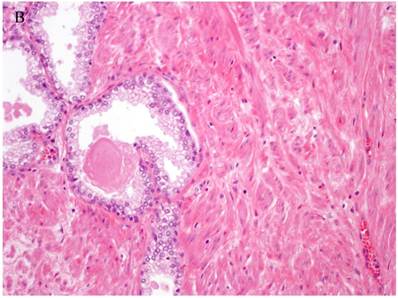

Figure 1

Patterns and heterogeneity in Cancerous Prostate Tissue (Hematoxylin and eosin stain). A. Normal prostate showing luminal and basal cells. B. Prostate cancer with definable glandular pattern, usually part of Gleason pattern 3. C. Prostate cancer with aggregation, clustering or individual infiltrating cells as described for Gleason 4.